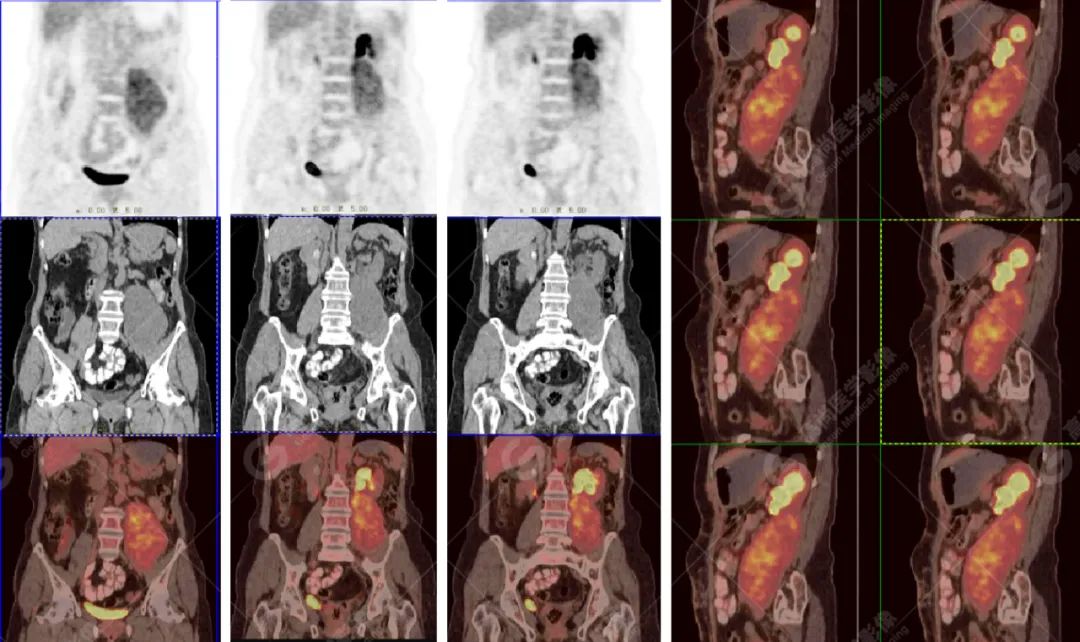

影像所见:左腹膜后间隙(原术区)见一长椭圆形软组织密度肿块影,范围约 8.0 cm×6.6 cm×15.8 cm,CT 值 30 Hu,FDG 高摄取,SUVmax5.0,考虑肿瘤复发,侵犯相邻左侧输尿管、腰大肌、后腹壁。

增强扫描肿瘤不均性中度强化,动、静脉期 CT 值:41 Hu、72 Hu(平扫 CT 值 30 Hu)。

CT 表现:大多数呈类圆形或不规则形,平扫大多数呈低密度,边界不清,内部密度不均匀,可见更低密度囊变坏死区,钙化非常少见。

增强扫描:肿瘤强化呈多样性,大多呈不均匀中度明显强化。

PET 表现:FDG 高摄取。

高级别 UPS:为多见类型,大多发生在四肢 (尤其下肢),其次腹膜后,大多位于深部 (筋膜下方) 软组织。影像上呈边界不清的类圆形或不规则团块状肿物,无明显包膜;肿瘤内常伴坏死、囊变,病灶实性部分呈等低混杂密度;增强扫描肿瘤实性部分呈中度不均匀强化。

对于四肢肌肉深部、腹膜后肿瘤,边缘呈卵圆形或体积较大分叶状或有大片液化坏死的囊实性肿块,瘤周有或无水肿带,周围组织受侵,增强扫描肿块实质呈轻、中度强化。结合患者好发年龄,病程进展较快,临床出现局部疼痛或功能障碍等表现,可以提示 UPS 可能。

PET/CT 检查可以全面了解肿瘤病灶范围,周围组织结构有无侵犯累及,其他部位有无转移。